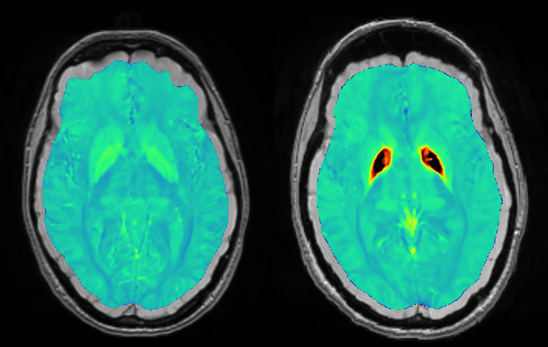

La susceptibilité magnétique indique la susceptibilité de la matière à s’aimanter dans un champ magnétique. A l’image d’une boussole qui s’oriente dans le champ magnétique terrestre, BriSE permet de mesurer l’aimantation des tissus dans le champ magnétique d’un IRM.

Notre innovation permet d’obtenir des images résolues et d’une sensibilité exceptionnelle pour orienter le diagnostic et mieux suivre les maladies neurologiques.

Notre technologie permet de visualiser très précisément les structures cérébrales impliquées dans la maladie et d’identifier les régions malades.

Notre technologie permet de visualiser de façon très précise ces signes et de les suivre dans le temps.

Certains enfants accumulent de façon anormale le fer dans leur cerveau. Cette accumulation est généralement due à une mutation dans un des gènes importants pour que le cerveau puissent utiliser le fer normalement. Notre technologie permet de mesurer la quantité de fer qui s’accumule dans le cerveau de ces jeunes malades.